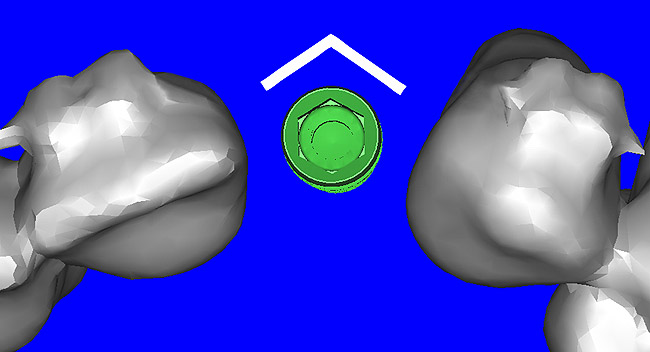

Using different masking (segmentation) and threshold Hounsfield unit values, several new 3D bone volumes can be created which offer invaluable information. To help determine the final position of each implant a new bone model was created with a Hounsfield unit value of 1480, which eliminated all but the densest objects included in the scan data. (Results may vary depending on the CBCT machine used.) The inner and outer layers of bone were removed, leaving the underlying enamel and root structure of the teeth (Figure 8A). After the bone had been stripped away, the root inclinations were examined closely. The most striking findings confirmed the rotated position of the right central, while revealing the slight mesial dilaceration of the root apex, which converged on the space needed for the path of the potential implant (Figure 8B). The schematic shapes of the proposed implants were visualized for the right and left lateral spaces in different rotations of the 3D maxillary arch. It was at this point that a determination was made as to the appropriate implant shape and type that would fit the available space while avoiding encroachment on adjacent tooth roots. A tapered design implant (Tapered Screw-Vent®, Zimmer Dental, www.zimmerdental.com) was chosen from the large virtual library. With the SIMPlant software, the virtual library contains data from dozens of implant manufacturers and realistic.computer-aided design representations as seen in Figure 9A through the translucent bone. The position of the left implant can be visualized with adequate mesial-distal distance between adjacent tooth roots (Figure 9B) and a more delicate placement (Figure 9C).

Figure 8a  By using the masking feature, the inner and outer layers of bone were removed virtually, revealing (A) the enamel and root structure of the teeth and the rotated position of the right central and (B) a slight mesial dilacerations of the root apex.

Figure 8a

Figure 8b  By using the masking feature, the inner and outer layers of bone were removed virtually, revealing (A) the enamel and root structure of the teeth and the rotated position of the right central and (B) a slight mesial dilacerations of the root apex.

Figure 8b

Figure 9a  Virtual implants were placed to determine the appropriate shape and type for the available space, in this case a tapered design allowed for adequate mesial-distal distance between adjacent roots.

Figure 9a

Figure 9b  Virtual implants were placed to determine the appropriate shape and type for the available space, in this case a tapered design allowed for adequate mesial-distal distance between adjacent roots.

Figure 9b

Figure 9c  Virtual implants were placed to determine the appropriate shape and type for the available space, in this case a tapered design allowed for adequate mesial-distal distance between adjacent roots.

Figure 9c